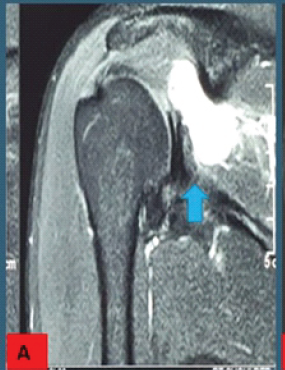

Painful Biceps Vincula: An Unrecognized Cause of Anterior Shoulder Pain

Alex E. White , Matthew R. Bryan , Christopher Fenelon , Samuel A. Taylor , Stephen J. O'Brien ………………………………p.463-467